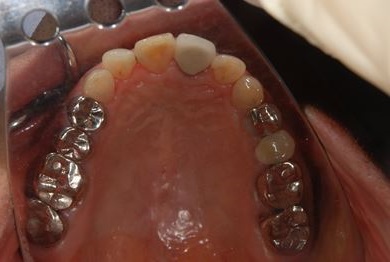

| 性別/年齢 | 男性 / 69歳 | ||||||||||||||||||||||||||||||||

| 主訴 | 1.左上奥歯の詰め物が取れた 2.左上前歯の欠け 3.右下奥歯の欠け | ||||||||||||||||||||||||||||||||

| 治療方針 | セラミック治療にて、審美的回復を行う。 | ||||||||||||||||||||||||||||||||

| 治療内容 | メタルボンドセラミッククラウン1本(メタルボンド用土台1本)、ハイブリッドセラミックインレー1本 | ||||||||||||||||||||||||||||||||

| 総治療費 | 172,410円 | ||||||||||||||||||||||||||||||||

| 治療期間 | 4ヶ月 |